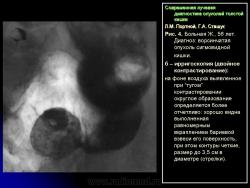

1) утолщение стенки, неровность контура и сужение просвета одного из участков кишки (рис. 5);

2) сохранение на расправленной от естественной складчатости поверхности слизистой кишки небольшого участка бариевой взвеси (типа звездочки или другой конфигурации) диаметром от 0,5 до 1,5 см – симптом ранних признаков опухоли (рис. 6);